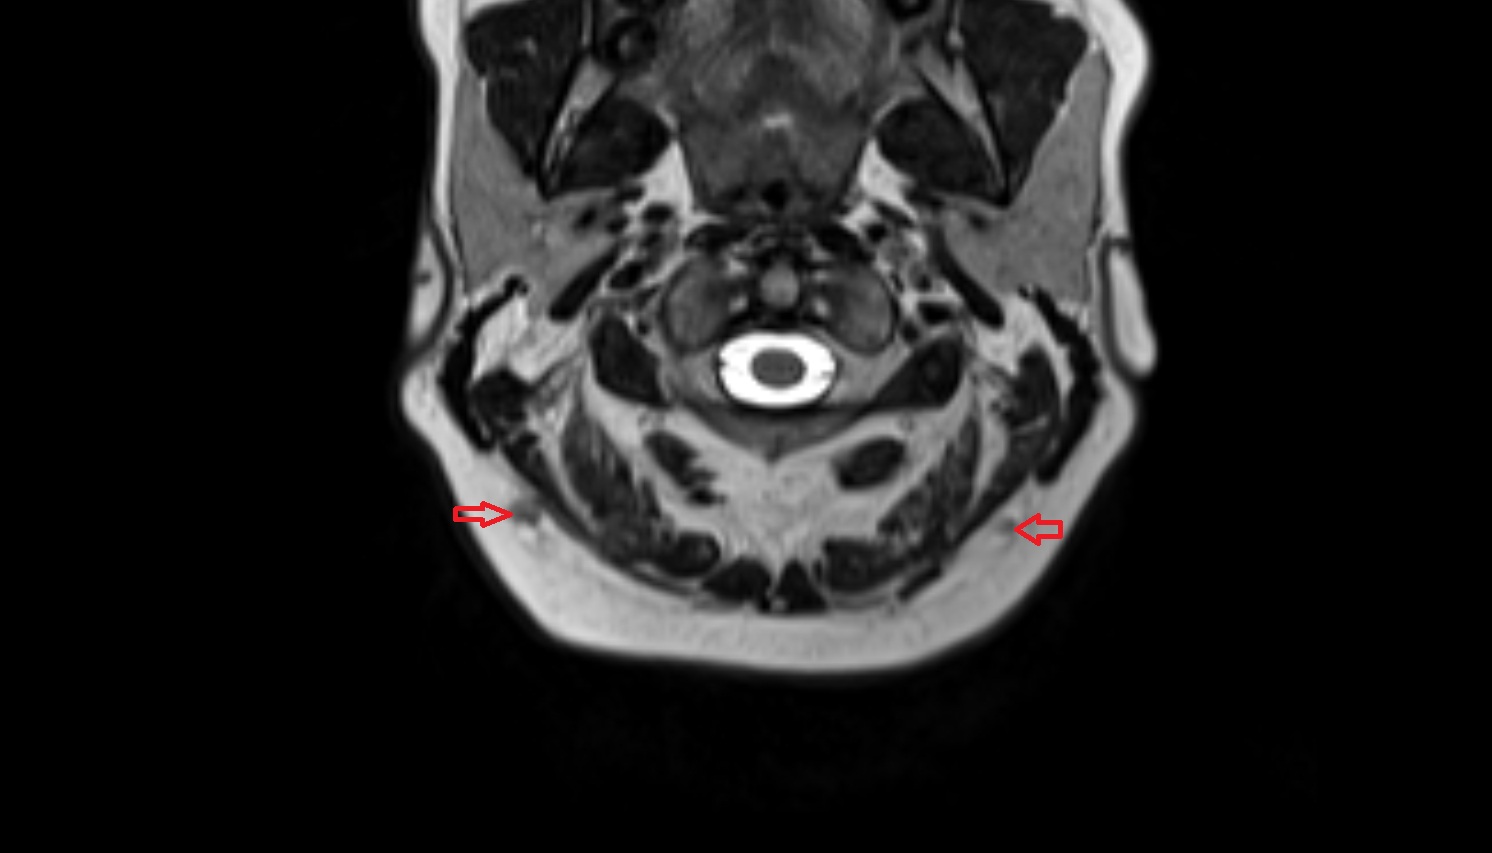

- Temporomandibular joint

- Mandibular condyle

- Mandibular fossa